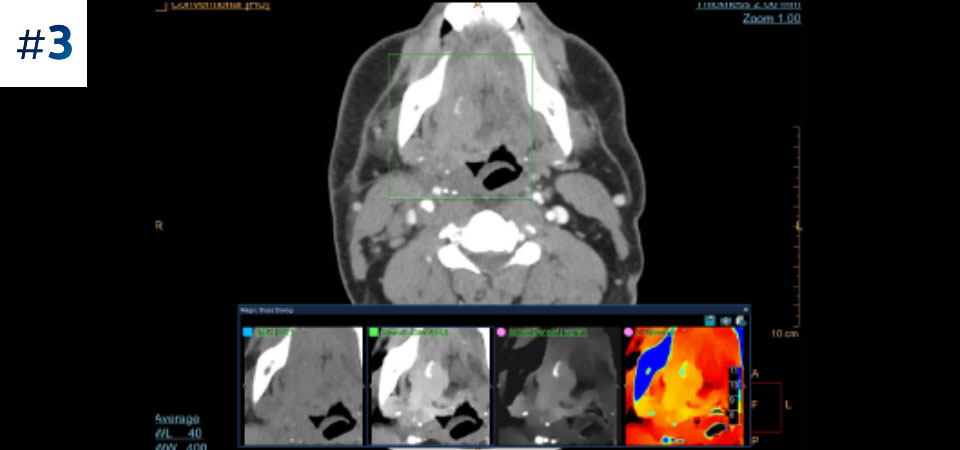

With detector-based spectral, you acquire multiple layers of data—conventional and spectral—within a single exposure and without special scan modes for improved tissue characterization and visualization.

Scan as usual A single scan for fast, low-dose conventional and spectral data for every patient, every time.

Always available 100% spectral, 100% of the time for results that are always available on-demand, even retrospectively.

Reduced follow-up exams Improved tissue characterization and visualization may reduce the need for follow-up scanning for sub-optimal exams and incidental findings.

See the difference between spectral-detector CT and conventional CT